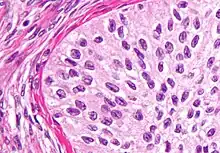

Clear cell tumors

Micrograph of an ovarian clear cell carcinoma. H&E stain.

Clear cell tumors are characterized by large epithelial cells with abundant clear cytoplasm and may be seen in association with endometriosis or endometrioid carcinoma of the ovary, bearing a resemblance to clear cell carcinoma of the endometrium. They may be predominantly solid or cystic. If solid, the clear cells tend to be arranged in sheets or tubules. In the cystic variety, the neoplastic cells make up the cyst lining.

Prognosis

These tumors tend to be aggressive, the five year survival rate for tumors confined to the ovaries is approximately 65%. If the tumor has spread beyond the ovary at diagnosis, the prognosis is poor